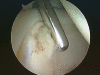

Femoroacetabular impingement is becoming increasingly recognised as a cause of hip pain in the young adult. It is thought that the condition may lead to acetabular labral tears, chondro-labral separation, chondral delamination and eventually predispose to osteoarthritis of the hip. Efforts have thus been directed to diagnosing and treating the underlying pathology and subsequent sequelae. This article presents the relevant literature with regards to the aetiology of femoroacetabular impingement, its clinical features, investigations and options of management. Finally outcomes relating to both open and arthroscopic approaches to treatment are discussed.